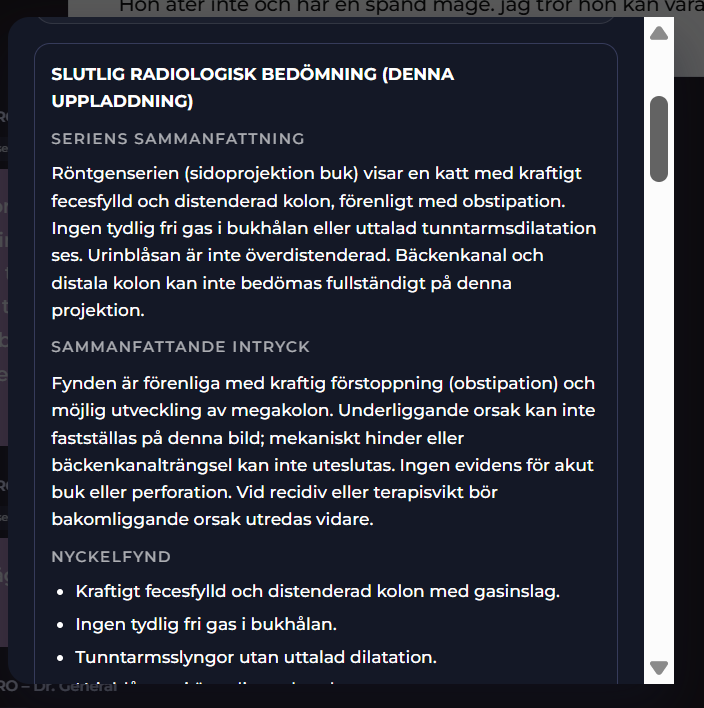

Radiologica Röntgentolk har utgått från chatt med din doktor som har en frågeställning som ska utredas. I detta exempel är det en katt som kan vara förstoppad. En komplett remiss har producerats. Remissens frågeställning tillsammans med röntgenbilder du kan ladda upp kommer att tolkas och generera ett remissvar.

Radiologica gör en tolkning av dina röntgenbilder

Radiologica tar emot uppladdade röntgenbilder samt remissens frågeställning och gör en analys. Du laddar upp röntgenbilden och klickar på Tolka bilder.

Radiologica - Komplett remisssvar

I Visuella fynd (Stetoskåpet) finner du det kompletta remisssvaret. I remisssvaret kan du du titta på den strukturerade labrapporten samt läsa Labora´s svar på frågeställningen. Labora kommer svara både övergripande och i detalj för de enskilda biomarkörerna smat ge en rekommendation till din chatt AI doktor.